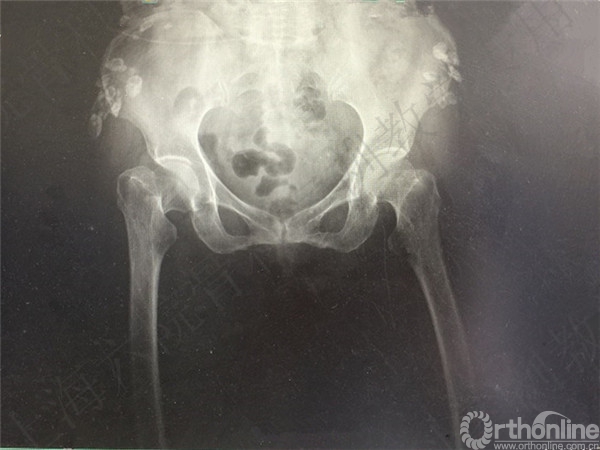

患者跌倒致右股骨颈骨折,择期行右全髋置换术。

术后2周患者自述夜间翻身至右髋疼痛。

急诊X线摄片示:右髋假体脱位,小粗隆骨折。